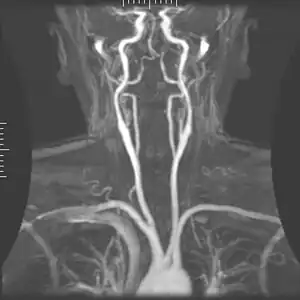

The condition and health of the external carotid arteries is usually evaluated using Doppler ultrasound, CT angiogram or phase contrast magnetic resonance imaging (PC-MRI). Typically, blood flow velocities in the external carotid artery are measured as peak systolic velocity (PSV) and end diastolic velocity (EDV).[4]

PSV values greater than 200 cm/s are considered to be predictive of more than 50% of external carotid artery stenosis.[5]

Additional images

Branches of external carotid artery

Branches of external carotid artery